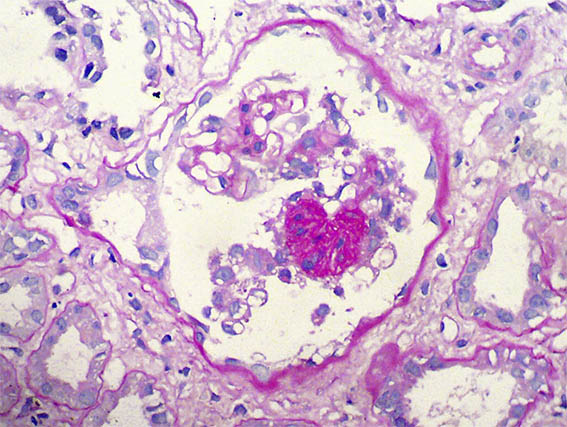

Figure 6. PAS, X400.